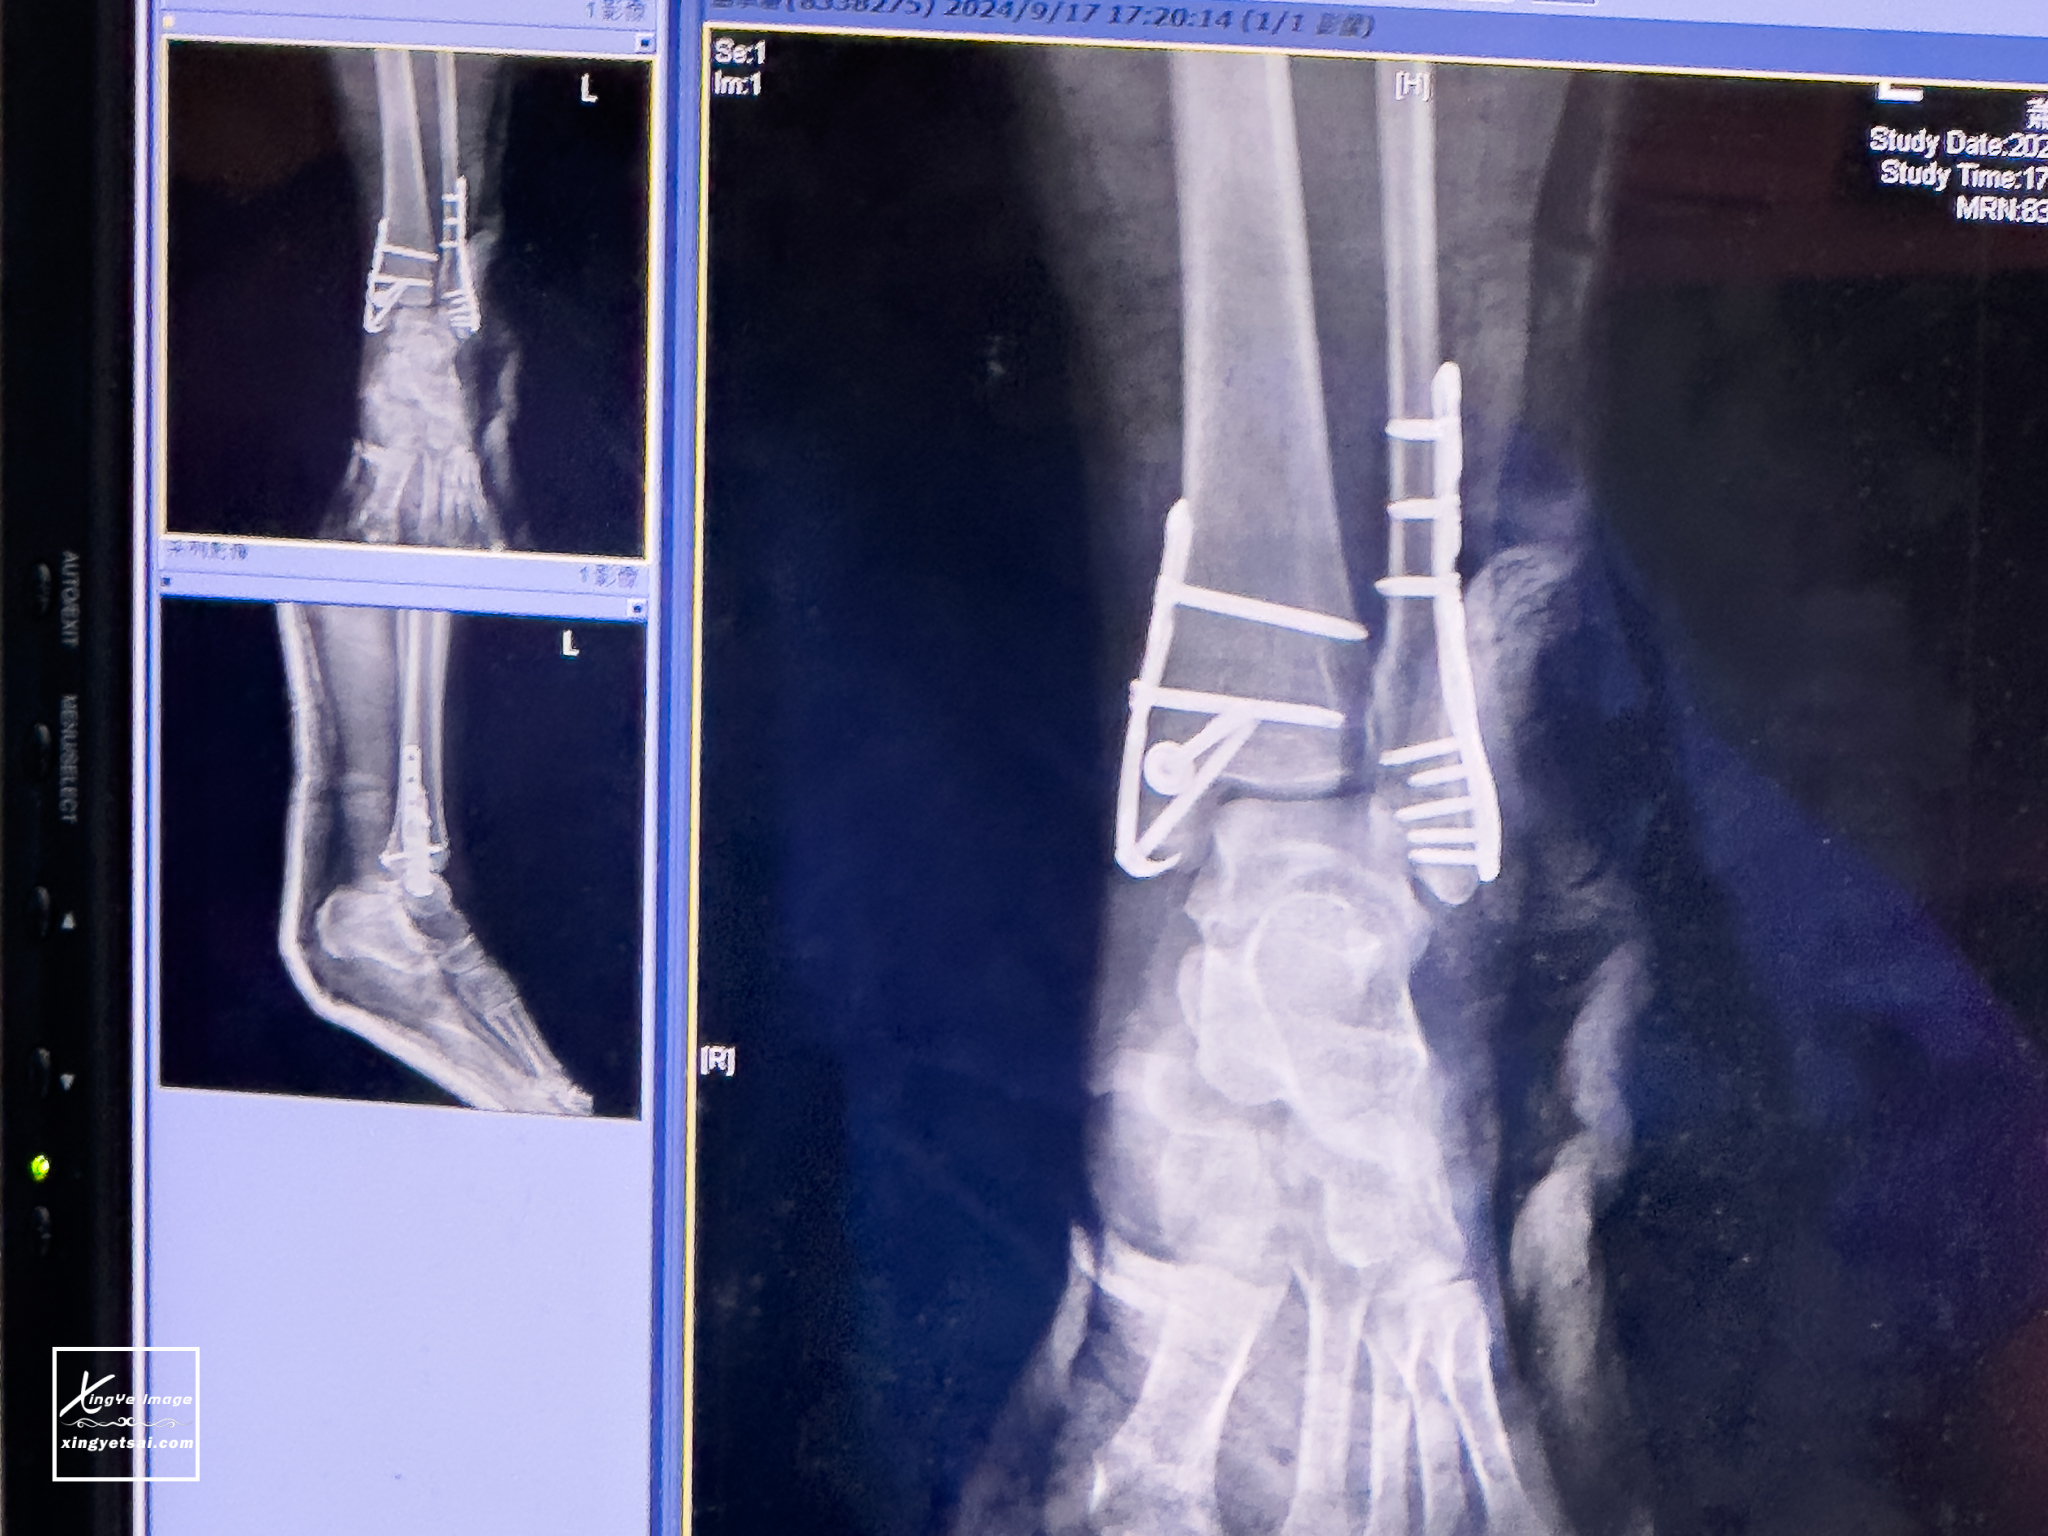

在急診照了X光,左踝關節三踝骨骨折,醫生說傷的挺嚴重,因為左踝關節的左側、右側與後踝都裂了。急診骨科醫師評估需開刀行內固定,自費鈦合金鋼板兩片(一根骨頭需一片),光自費兩片鋼板耗材費用NT$111700,別吃驚,這已經是最便宜的了,以前沒特別在意,竟不知道原來骨傷這麼貴

在健保與醫療體系的支援,很幸運當天下午就馬上安排了手術,左腳踝2條各7-8公分的傷口,真的很心痛,希望未來會引以為戒,小心還要更小心,畢竟,真的沒人知道,我只是回娘家過中秋節,在如此熟悉的地方,竟然會摔傷成這樣。

▲住院約一周,總花費為12萬多,其中自費鈦合金鋼板兩片(一根骨頭需一片),兩片鋼板耗材費用就佔了NT$111700